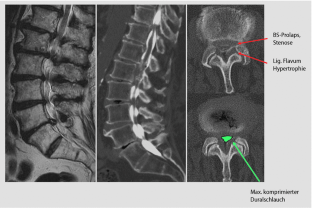

Abb. 4